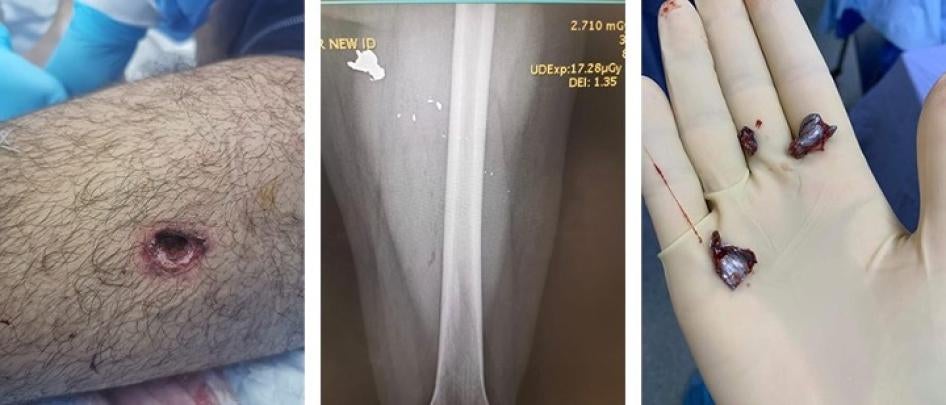

Security forces fired a bullet at Omar that hit his upper left thigh. The image on the left shows the entrance wound. The X-ray shows three large bullet fragments and several smaller fragments in his left leg, and the image on the right shows the fragments extracted from his leg. © 2020 Courtesy of Omar

Human Rights Watch reviewed Omar’s medical records from August 8, including X-rays, which showed three large bullet fragments and several smaller fragments in his left leg. “Fortunately, it didn’t hit my bone,” he said. “It was close to an artery, but it narrowly missed it.”